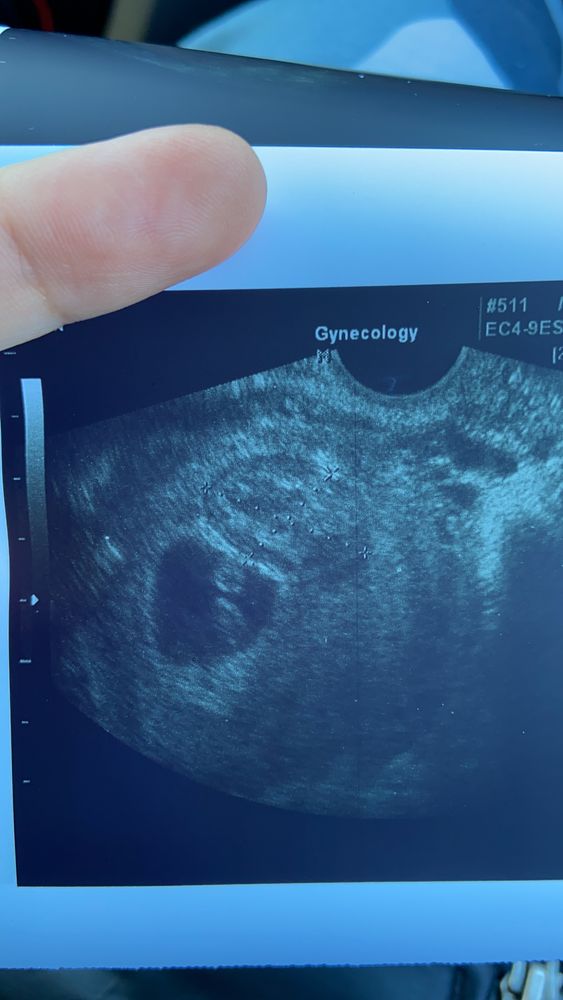

Хорошие новости

Сходила сегодня на очередное узи.. сердцебиение в норме. Кто 12мм… растёт малыш. Гематома реорганизуется.